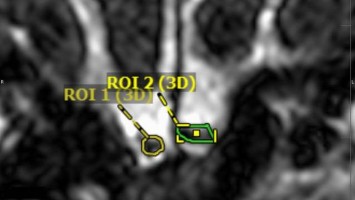

Wie Riechstörungen objektiv messbar werden

Riechstörungen, die im Kontext eines Arbeitsunfalls auftreten, sind häufig schwer eindeutig zu begutachten. Eine Volumetrie des Bulbus olfactorius (BO) könnte hier eine zuverlässige und objektive Methode sein, um die Funktion des Riechsinns zu evaluieren. Wie ist sie anzuwenden, und welche Fallstricke gibt es?

Kutane Arzneimittelreaktion/© Hötzenecker, W., Heimlich-Manöver/© Widmer, N; Heimes, D / all rights reserved Springer Medizin Verlag GmbH, Aufbau bei einer endoskopische Mittelohrchirurgie/© Mir-Salim P., Berlin, Wespen auf Stein/© merlion / Getty Images / iStock (Symbolbild), Schilddrüse einer Patientin wird untersucht/© Werner / stock.adobe.com (Symbolbild mit Fotmodellen), Volumetrie des Bulbus olfactorius/© Keweloh S.. et al. doi.org/10.1007/s00106-025-01650-z unter CC-BY 4.0, Augen und Nase einer Frau/© AlexanderFord / Getty Images / iStock (Symbolbild mit Fotomodell), Eine ältere Frau schaut in die Ferne/© RgStudio / Getty Images / iStock (Symbolbild mit Fotomodell), Transnasales Ösophagoskop/© F. Michel, Seeheim-Jugenheim, Ex vivo konfokales Laserscanmikroskopiebild eines Morbus Bowen/© Grunewald S et al. / all rights reserved Springer Medizin Verlag GmbH, Einweckglas mit Hering/© FoodieMedia / Getty Images / iStock (Symbolbild), Zwei Injektionspens mit Semaglutid/© Kassandra / Stock.adobe.com, Gewitter mit Blitzschlag/© solarseven / Getty images / iStock, Ulzerative Form des oralen Lichen planus/© Abdusalamov K. et al. doi.org/10.1007/s00105-025-05540-x unter CC-BY 4.0, Otitis externa/© Dr. P. Marazzi / Science Photo Library (Symbolbild), VMAT-Bestrahlungsplan einer definitiven Radiochemotherapie eines linksseitigen, lokal fortgeschrittenen Tonsillenkarzinoms/© Schnellhardt, S et al. / all rights reserved Springer Medizin Verlag GmbH, Frau hustet/© Suzi Media Production / Getty Images / iStock (Symbolbild mit Fotomodell), Tympanometrie bei einer Frau/© Viacheslav Yakobchuk (Symbolbild mit Fotomodell), Stimmlippeninjektion in der HNO-Praxis/© Markus Hess, Mann erhält eine Spritze im Gesicht/© Alvaro / Stock.adobe.com (Symbolbild mit Fotomodell), Ein Arzt sprüht ein antimikrobielles und entzündungshemmendes Spray in den entzündeten Hals eines Mädchens./© HENADZY / Stock.adobe.com (Symbolbild mit Fotomodell), Junger Mensch bekommt Spritze verabreicht/© mapo / Getty Images / iStock (Symbolbild mit Fotomodellen), Bestrahlungsplans einer Wirbelsäulenmetastase eines oligometastasierten Prostatakarzinoms/© Springer Medizin Verlag GmbH, Cholesterolgranulom im MRT/© Frederik F/ all rights reserved Springer Medizin Verlag GmbH, Schimmelbefall an der Wand/© Bigy / Stock.adobe.com (Symbolbild), Rasterelektronenmikroskopische Aufnahme von Nanopartikeln/© Hansen S. et al. doi.org/10.1007/s00106-025-01633-0 unter CC-BY 4.0, Medulläres Schilddrüsenkarzinom linker Schilddrüsenlappen in der Sonographie/© Lorenz K et al. / all rights reserved Springer Medizin Verlag GmbH, Sonnenhüte (Echinacea)/© Wieland Teixeira / Getty Images / iStock (Symbolbild mit Fotomodell), Körperstereotaxie einer Lebermetastase im Segment VIII am MR-LINAC/© Ehret, F. et al. / all rights reserved Springer Medizin Verlag GmbH, Eine ältere Frau riecht an einem Basilikumblatt/© Halfpoint / Stock.adobe.com (Symbolbild mit Fotomodell), Mann hustet/© kostyha / stock.adobe.com (Symbolbild mit Fotomodell), Titel/© J. Hornung, Erlangen, Senior hält sich vor Schmerzen an den Hals/© brizmaker / Getty Images / iStock (Symbolbild mit Fotomodell), Chor von älteren Menschen/© Highwaystarz-Photography / Getty (Symbolbild mit Fotomodellen), Eine junge Frau spült sich mir einer Nasenspülung die Nase/© puhhha / Getty Images / iStock (Symbolbild mit Fotomodell), Kleiner Junge mit Pille auf der Zunge/© redpepper82 / stock.adobe.com (Symbolbild mit Fotomodell), Frau mit Kopfschmerzen/© MaximFesenko / Getty Images / iStock (Symbolbild mit Fotomodell), Normaler Verlauf nach Hirntumor?/© Wolfgang Freund, Szintigraphie der Schilddrüse mit zwei Knoten/© AniphaeS / Getty Images / iStock, Patient mit Bauchschmerzen beim Arzt/© anon / Stock.adobe.com (Ausschnitt; Symbolbild mit Fotomodellen), Mann erleidet Schwindel/© Tunatura / Getty Images / iStock (Symbolbild mit Fotomodell), Ärztin untersucht ältere Frau/© peopleimages.com / stock.adobe.com (Symbolbild mit Fotomodellen), Infusion/© georgeoprea9 / Getty Images / iStock, Frau wird Blut abgenommen/© andresr / Getty Images / iStock (Symbolbild mit Fotomodellen), Junge Ärztin vor einem Triage-Zelt/© Milos / Stock.adobe.com (Symbolbild mit Fotomodell)